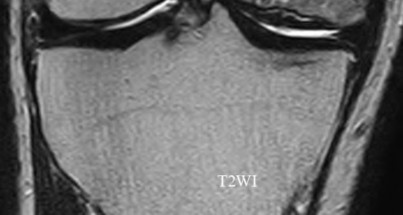

Question 4:

A 55-year-old woman feels a 'pop' in the back of her knee while squatting. An MRI is shown: A posterior horn medial meniscus root tear is identified. Biomechanically, a complete medial meniscus posterior root tear alters contact pressures to a degree equivalent to which of the following?

Correct Answer: Total meniscectomy

Explanation:

A complete posterior root tear of the medial meniscus leads to a complete loss of hoop stresses, resulting in meniscal extrusion. Biomechanically, this alters peak tibiofemoral contact pressures and reduces contact area to a degree equivalent to a total meniscectomy, leading to rapid articular cartilage degeneration.